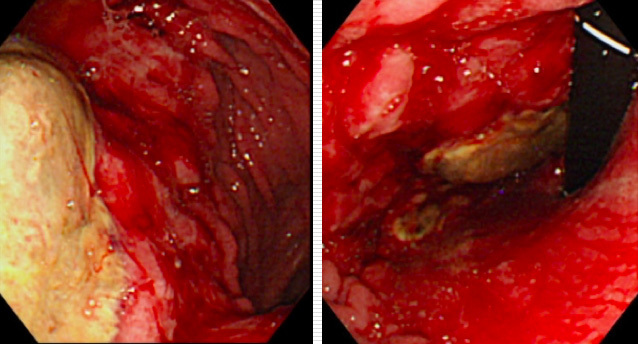

例えば、腹腔動脈合併尾側膵切除の手術を受けた患者さんは、術後に胃の血流不足から粘膜が出血したり壊死(組織が死滅する)したりする虚血性胃症を発症してしまうことがあります。この虚血性胃症の治療には長い場合は数か月を要します。この間は抗がん剤による治療もできないため、患者さんの不利益になってしまいます。このように患者さんの生存率を低下させるような合併症を減らすことは、この手術の大きな課題です。